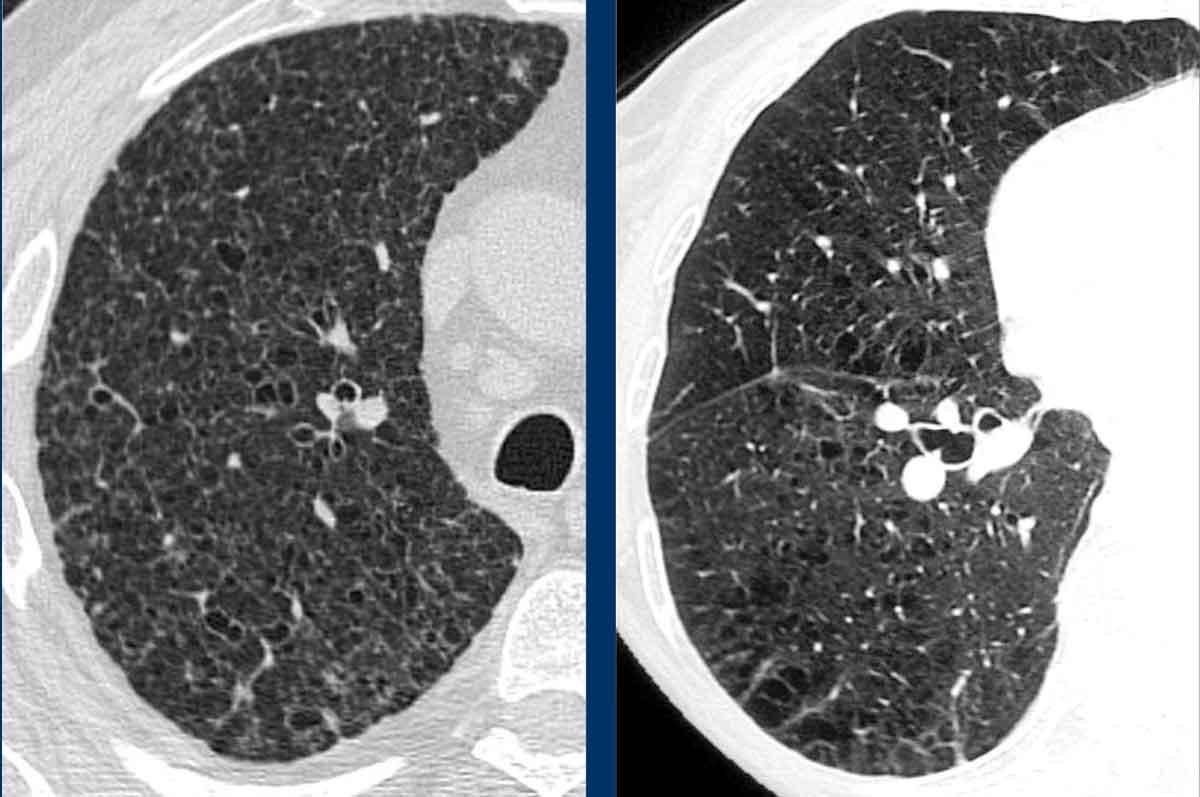

LAM biểu hiện với số lượng lớn các nang hình tròn, bờ đều đặn, phân bố rải rác khắp nhu mô phổi.

Hình ảnh

- Nhiều nang ở một phụ nữ trẻ. Lưu ý hình dạng tròn đều và phân bố lan tỏa.

- Trường hợp LAM nặng. Khi có tiền sử hút thuốc lá, chẩn đoán phân biệt cần đặt ra là LCH (giai đoạn tiến triển).

- Tràn dịch màng phổi (dịch dưỡng chấp) ở bệnh nhân LAM.

- Phân bố lan tỏa trong LAM.

Các hình ảnh này thuộc về một phụ nữ 39 tuổi với triệu chứng khó thở.

Chẩn đoán có khả năng nhất là gì?

Nhận xét hình ảnh

Có nhiều nang thành mỏng.

Lưu ý các nang phân bố đều khắp hai phổi.

Các ngách màng phổi cũng bị tổn thương (mũi tên).

Điều này cho phép loại trừ chẩn đoán LCH.

Chẩn đoán có khả năng nhất là LAM.

Đây là một ví dụ khác của LAM.

Có nhiều nang thành mỏng phân bố đều khắp hai phổi, điển hình cho LAM, nhưng trong trường hợp này kết hợp với tràn dịch màng phổi bên phải (mũi tên).

Các tế bào LAM có thể gây tắc nghẽn hệ thống bạch huyết trong lồng ngực và tạo ra tràn dịch màng phổi dưỡng chấp.

LAM là bệnh phổi dạng nang duy nhất có thể thấy sự kết hợp giữa các nang và tràn dịch màng phổi.

Ngoài ra, nhiều u cơ mỡ mạch máu (angiomyolipoma) được phát hiện ở vùng bụng trên.

Bệnh nhân này được xác định mắc LAM liên quan đến phức hợp xơ cứng củ (TSC – tuberous sclerosis complex).

Tỷ lệ hiện mắc u cơ mỡ mạch máu trong LAM tản phát là 40-50% và trong LAM liên quan TSC vào khoảng 80%.

Đây là trường hợp LAM nặng với nhu mô phổi bị tổn thương lan tỏa.